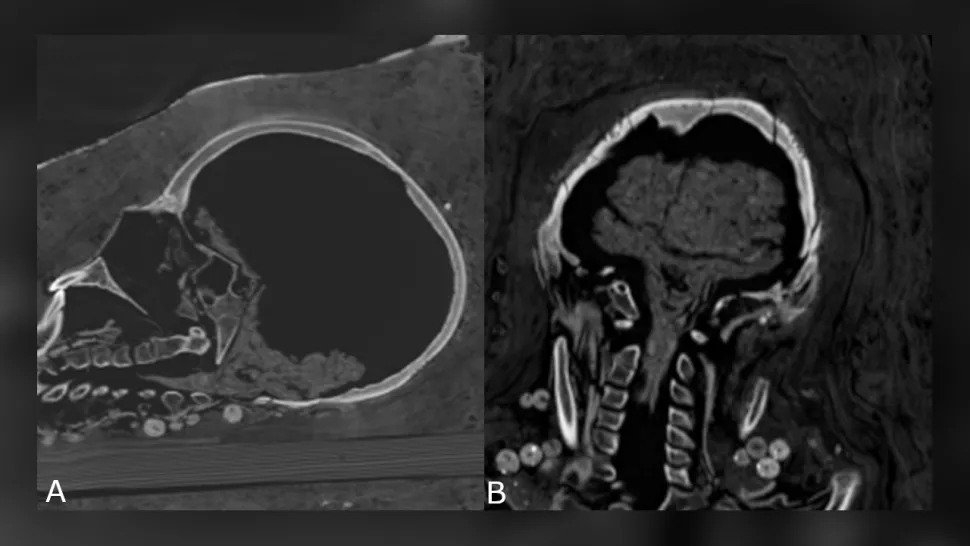

女性の脳も保存されていませんでしたが、青年の脳は保存されていました-縮小しましたが、脳と脳幹はまだ識別できました-そして青年の他の内臓も存在していました。

十代の脳を縮小します。 (Zesh et al。、PLOS One、2020)

「[脱水混合物]ナトロンからのある種の脱水のためにのみ、ミイラが生き残った可能性が非常に高いです。」

「これらのミイラは脳や内臓が取り除かれていなかったと確信している」とXesh氏は語った。